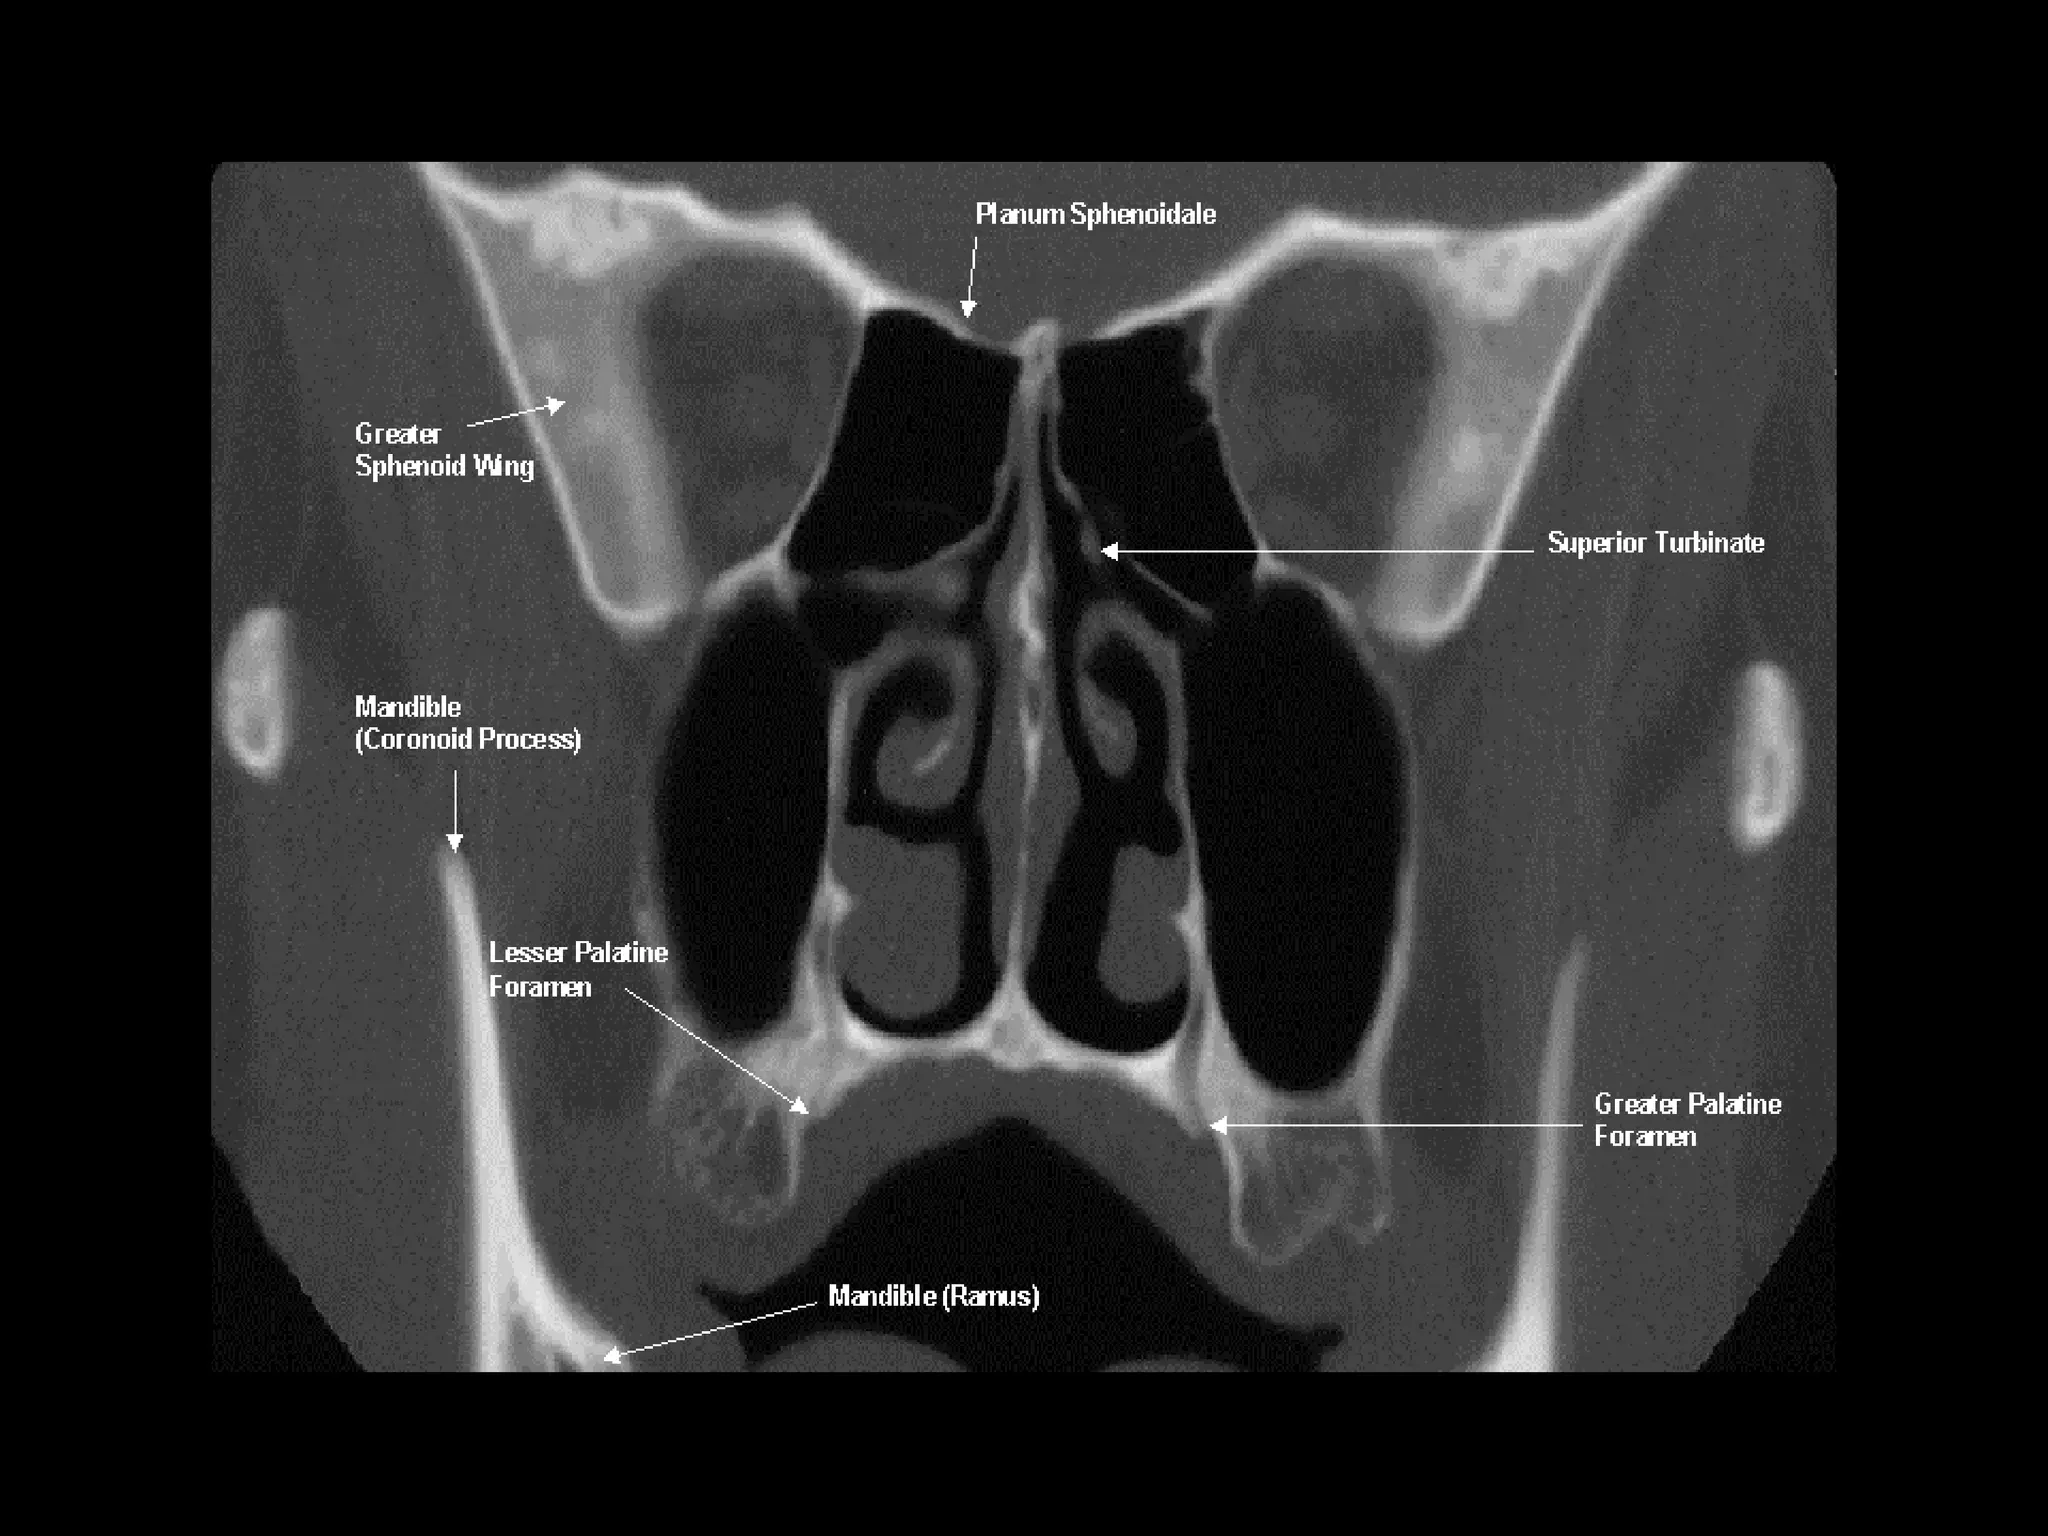

Radiographers are medical professionals who perform diagnostic imaging examinations and procedures to help physicians diagnose and treat diseases. They work under the supervision of radiologists to operate X-ray, CT, MRI, ultrasound and other medical imaging equipment and must have a strong understanding of human anatomy and pathology. Radiographers are responsible for correctly positioning patients, ensuring proper imaging techniques are used, and evaluating the quality of the resulting images.